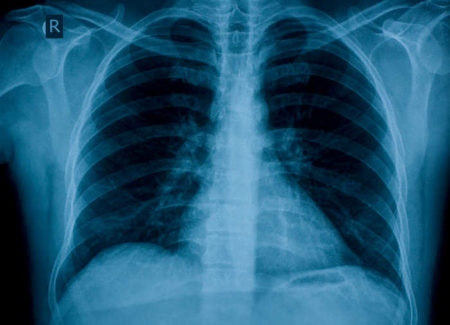

I volontari saranno divisi in 4 gruppi, tre attivi e uno di controllo. Un primo gruppo seguirà il programma completo, un secondo seguirà solo il percorso di cessazione dal fumo con citisina e il terzo riceverà la cardioaspirina, la dieta personalizzata e il programma di attività fisica. Il gruppo di controllo riceverà invece dei suggerimenti per un corretto stile di vita in base alle linee guida internazionali. Tutti saranno sottoposti una volta all’anno a una Tac spirale toracica a basse dosi di radiazioni, che è stato dimostrato essere un valido esame di screening per la diagnosi precoce del cancro del polmone nei forti fumatori. Inoltre verranno misurati periodicamente i valori della PCR nel sangue e, annualmente, verrà eseguito il test per le miRNA, piccolissime molecole molto specifiche che vengono rilasciate dall’organo aggredito dalla malattia e dal sistema immunitario e che, insieme ad altri fattori, possono permettere una diagnosi estremamente precoce, come stanno dimostrando altri studi in corso presso l’istituto.

Fino a oggi non esisteva un esame che permettesse la diagnosi precoce del tumore al polmone (i programmi di screening nazionali, infatti, esistono solo per il tumore al seno, per la cervice uterina e per il colon). A cambiare il punto di vista potrebbero essere i recentissimi dati degli studi Mild, condotto all’Int, e Nelson, presentati a settembre a Toronto, alla Conferenza mondiale dell’International Association for the Study of Lung Cancer. È stato dimostrato che un programma prolungato di screening con Tac spirale può ridurre la mortalità di oltre il 25% rispetto alla sola osservazione senza esami diagnostici. In particolare, Mild ha arruolato finora oltre 4mila forti fumatori ed è l’unico programma randomizzato di screening al mondo in cui la Tac spirale toracica sia stata eseguita, con frequenza annuale o biennale, per un periodo di 10 anni. “Sono risultati importanti, a riprova del fatto che è tempo di avviare sul territorio nazionale programmi di screening rivolti ai forti fumatori over 50, la fascia più a rischio di carcinoma polmonare”, sottolinea Giovanni Apolone, Direttore scientifico INT. L’apparecchiatura TAC spirale toracica è di ultima generazione e l’INT è tra i primi a utilizzarla al mondo. “Tra i vantaggi attesi, aggiunge Alfonso Vittorio Marchianò, Direttore Dipartimento Diagnostica per Immagini e Radioterapia INT – ci sono una straordinaria rapidità di esecuzione e, aspetto ancora più importante, l’esposizione, per la persona che si sottopone all’esame, a una dose minima di radiazioni, senza compromissione della qualità delle immagini”. Uno dei problemi maggiori dei programmi di screening sono le sovradiagnosi.